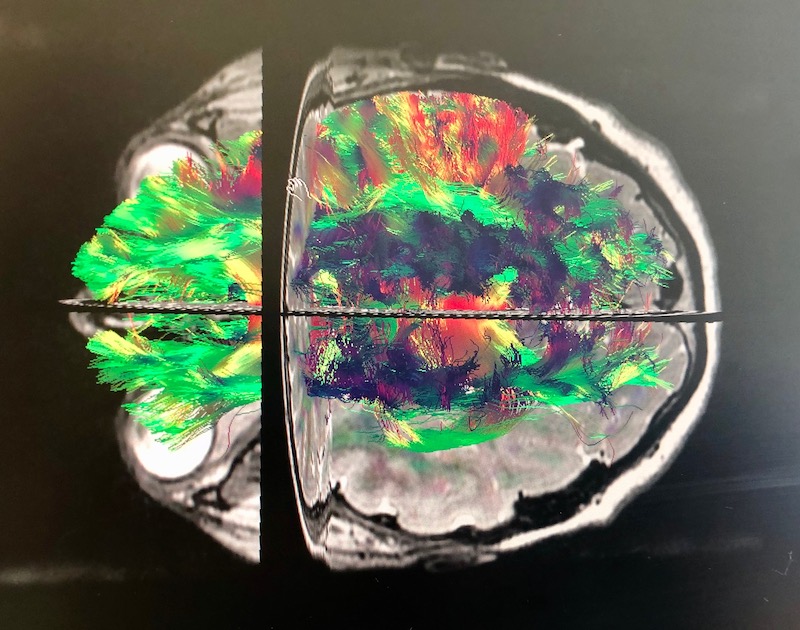

Najważniejszym punktem tego dnia była jednak wizyta na Oddziale Neurochirurgii Dziecięcej, podczas której dr Marek Lickendorf – neurochirurg, a zarazem jeden ze współzałożycieli ZGM – zaprezentował chłopcu, jak działa neuronawigacja kręgosłupowa i głowowa oraz stacja planowania traktografii. Dlaczego właśnie takie sprzęty?

– Aparatura, którą chcieliśmy pokazać Kacprowi, wykorzystuje specjalistyczne programy informatyczne – tłumaczy dr Marek Lickendorf. – Na przykład neuronawigacja to system komputerowy wykorzystywany w polu operacyjnym do nawigowania po kręgosłupie lub po mózgu. Pozwala precyzyjnie zaplanować i przygotować się do operacji, a następnie podczas zabiegu przeprowadzić ten plan, tak aby jak najmniej uszkodzić ważne struktury nerwowe – wyjaśniał młodemu wolontariuszowi doktor Lickendorf.